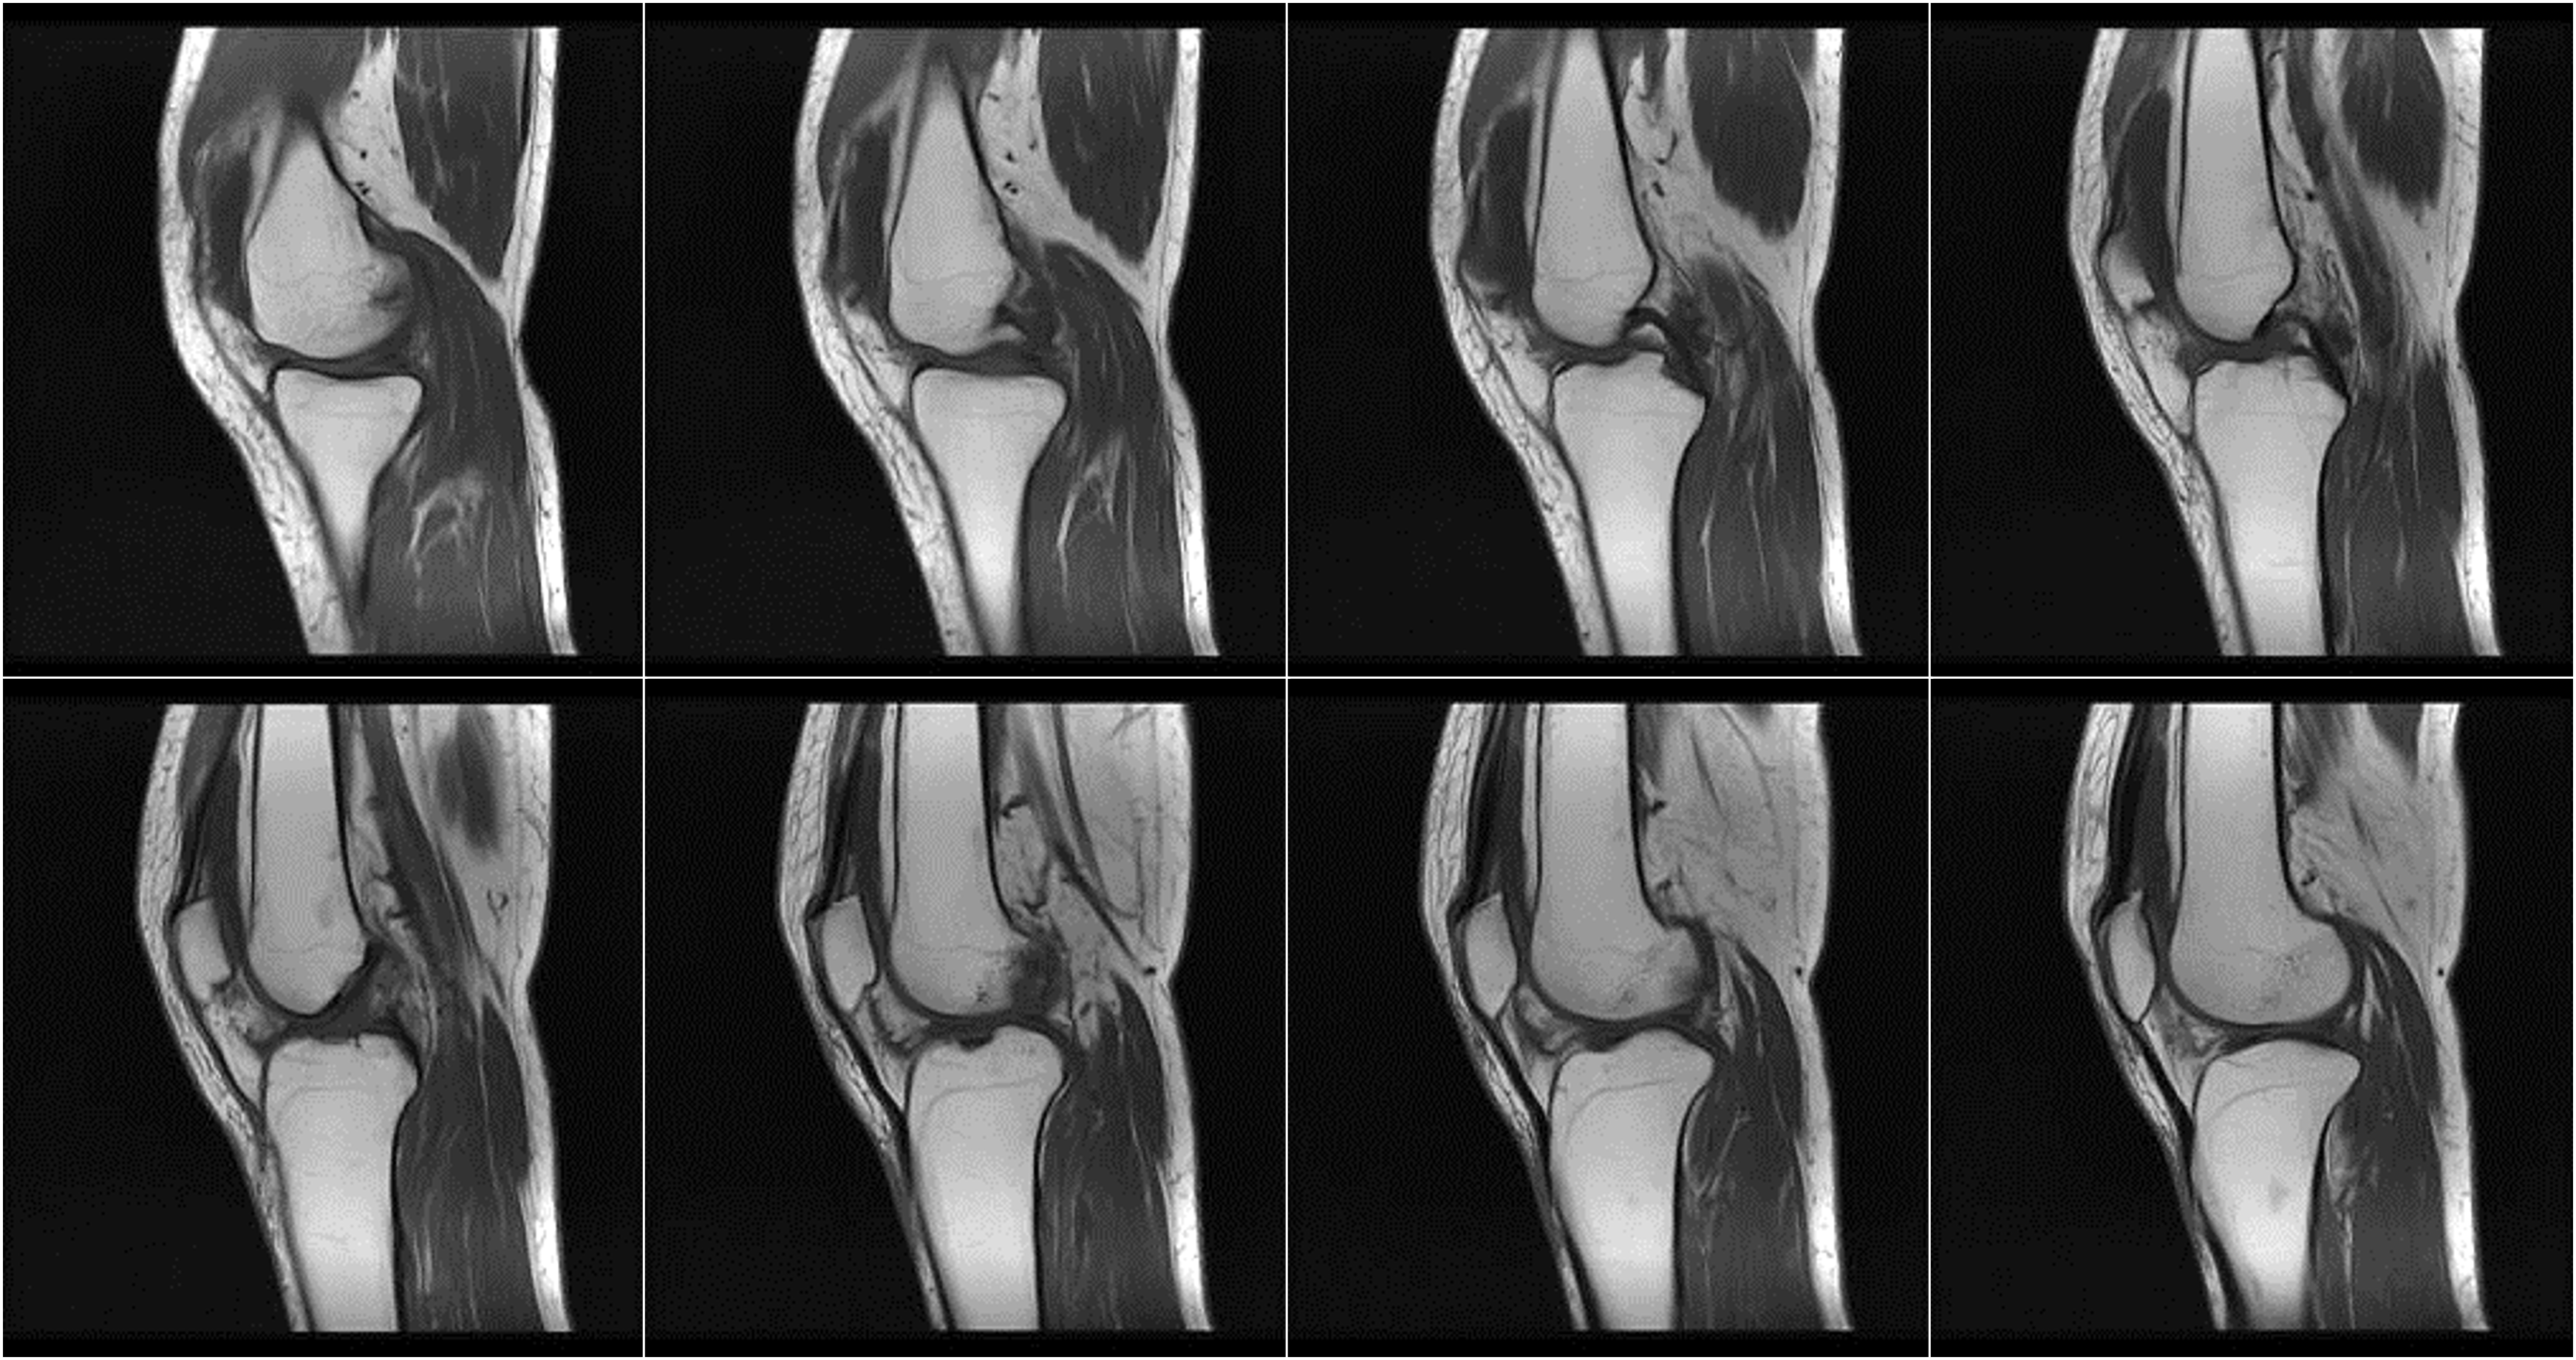

Mang lại trải nghiệm chụp yên tĩnh, thoải mái cho các ca thần kinh và chỉnh hình

Hình ảnh lâm sàng